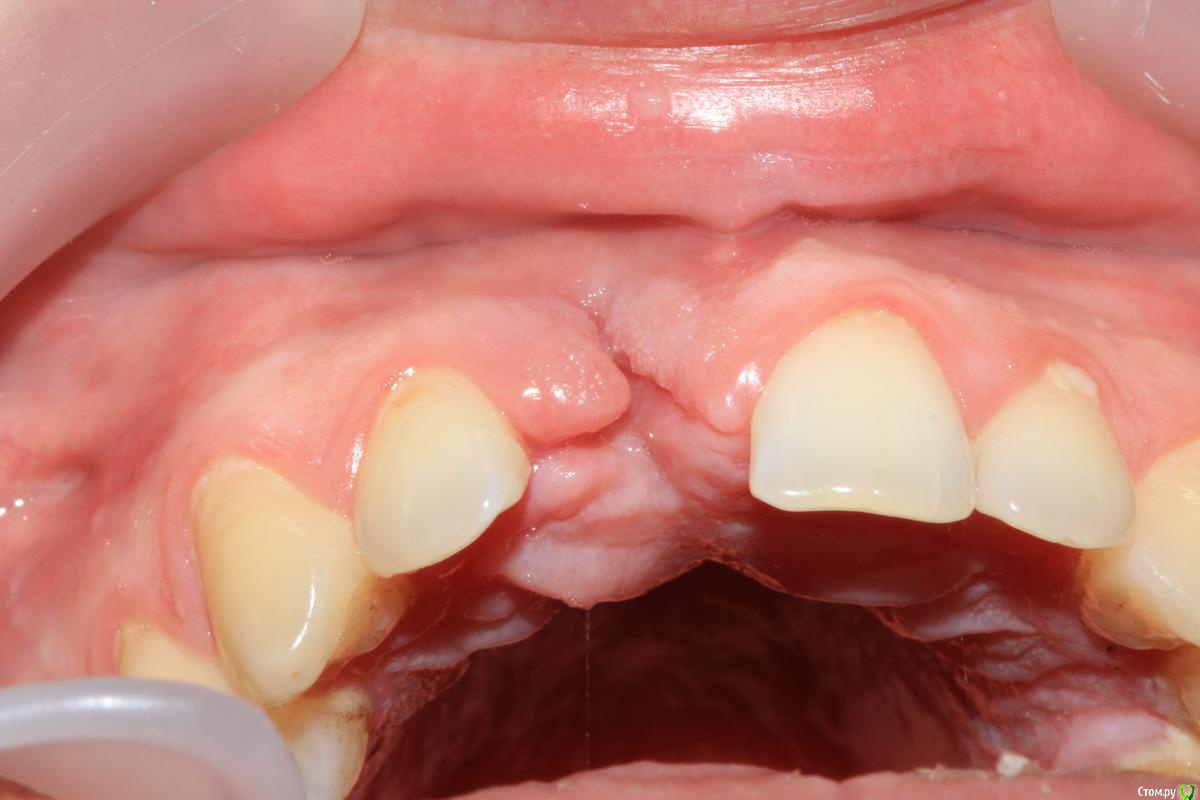

Dc.Petrov Опубликовано 4 мая, 2016 Поделиться Опубликовано 4 мая, 2016 Травма около 2 мес назад + травматичное удаление. Итог на фото.12 неподвижен. Вопрос : удастся ли с помощью нкр сделать кость для имплантации? Ссылка на комментарий

Dc.Petrov Опубликовано 5 мая, 2016 Автор Поделиться Опубликовано 5 мая, 2016 Предполагаю следующий алгоритм:1. Удаление 12 + НКР+ VIP2. Через 5 мес имплантация 11+ ССТ+времяшка3. Постоянное протезирование с консолем на 12. Поправьте,пжста, в чем ошибаюсь. Или как бы Вы поступили в данном случае Ссылка на комментарий

syrovovec Опубликовано 5 мая, 2016 Поделиться Опубликовано 5 мая, 2016 Наверное также.Или может так:УдалениеМягкотканнаяНКРИмплантация +сст и времяшка 1 Ссылка на комментарий